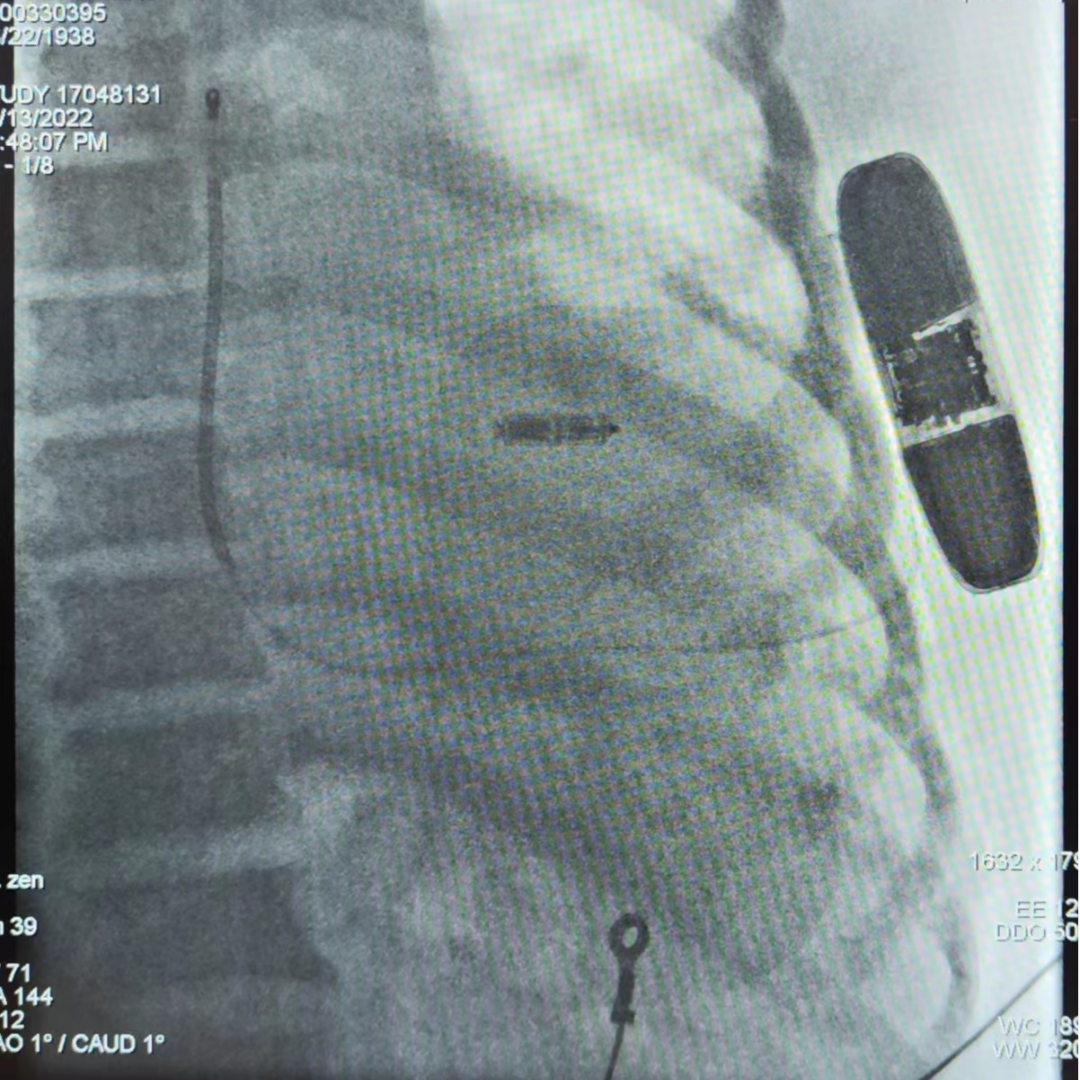

手术在全麻和深度镇静下进行,常规消毒、铺巾。取左腋中线第5-6肋为预定点,切开一约5cm的切口,逐层分离至皮下,分离囊袋至背阔肌与前锯肌之间。再次于剑突左上缘1cm为预定点,切开一长约2cm切口,逐层分离至深筋膜层,预埋两根缝合线,用导引针于切口间建立隧道,后引导除颤电极于皮下,固定除颤电极。用导引针导引除颤电极于深筋膜层至胸骨上窝位置,固定脉冲发生器于深筋膜层。进行除颤测试,采用50Hz,200mA交流电方式诱发室颤,SICD正确识别,经首次65J除颤成功,除颤阻抗74Ω,缝合皮肤,术区纱布覆盖,包扎,弹力绷带加压包扎止血。随后,通过股静脉穿刺,递送系统顺利定位室间隔,micra一次释放到位,成功将无导线起搏器通过导管植入到心腔内部,随之进行牵拉试验,验证了micra四个钩齿牢固地卡入心肌组织,通过不间断的心电系统检测,阈值0.38V,感知12.2mv,阻抗700Ω。整个手术过程顺利,仅耗时约2小时。

AP

LAO